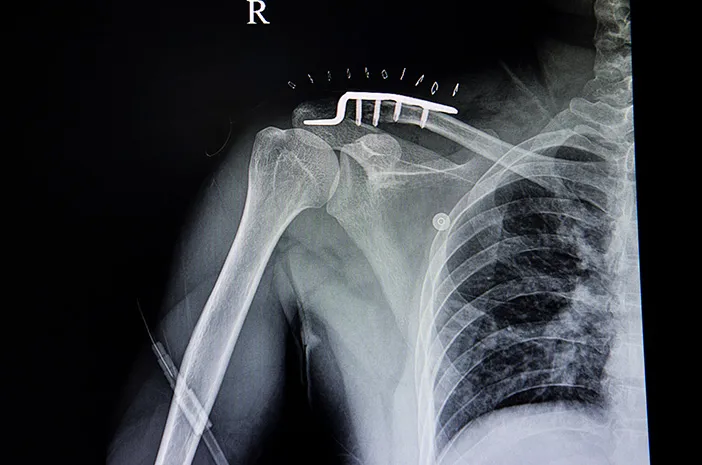

Operasi pasang pen adalah tindakan medis memasang alat bantu berupa pen atau plat logam ke dalam tulang yang mengalami patah.

Pen ini berfungsi untuk menstabilkan tulang agar posisinya tetap benar selama proses penyembuhan. Dengan pen, tulang yang patah bisa tumbuh dan menyatu dengan baik tanpa bergeser.

Pen yang dipasang biasanya terbuat dari bahan stainless steel atau titanium yang kuat dan tahan karat.

Alat ini dipasang di bawah kulit, menempel langsung pada tulang dengan menggunakan sekrup khusus.

Prosedur ini biasanya dilakukan oleh dokter spesialis ortopedi dengan menggunakan alat bantu sinar-X untuk memastikan posisi pen yang tepat.